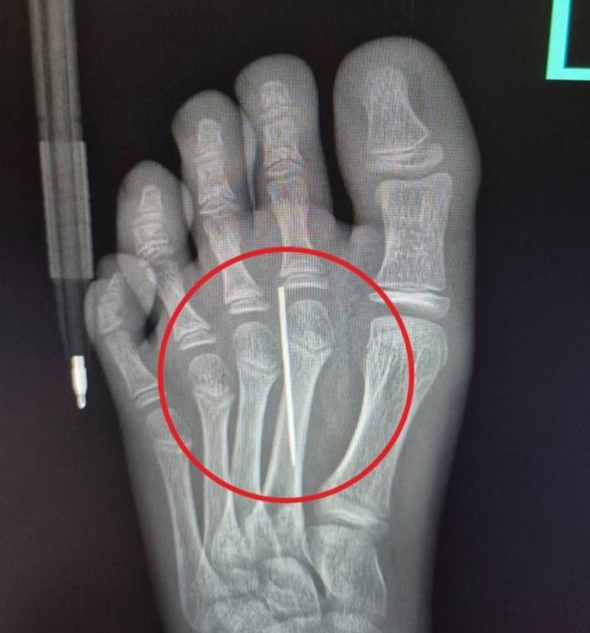

«Мы сделали рентген, который подтвердил наличие инородного тела в стопе, достали иголку специальным инструментом „Москит“. Процедура длилась не больше трех минут и прошла успешно», — рассказал заведующий травматологическим пунктом Артем Лисенков.